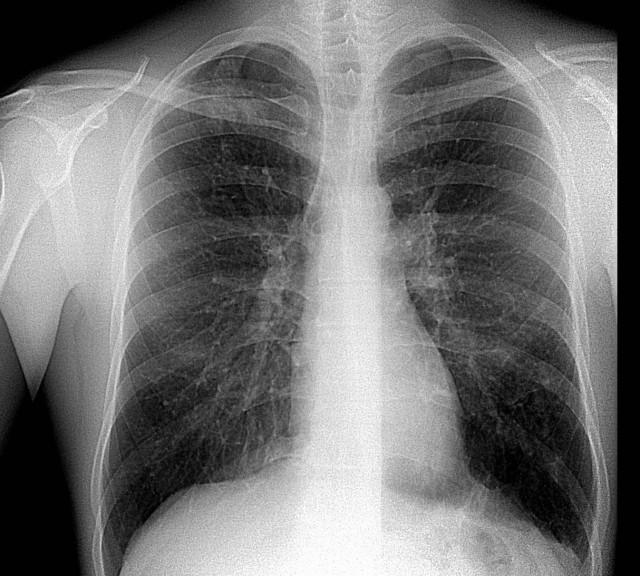

Рентген здоровых легких: примеры снимков и советы

Раздел: Сокровищница опыта